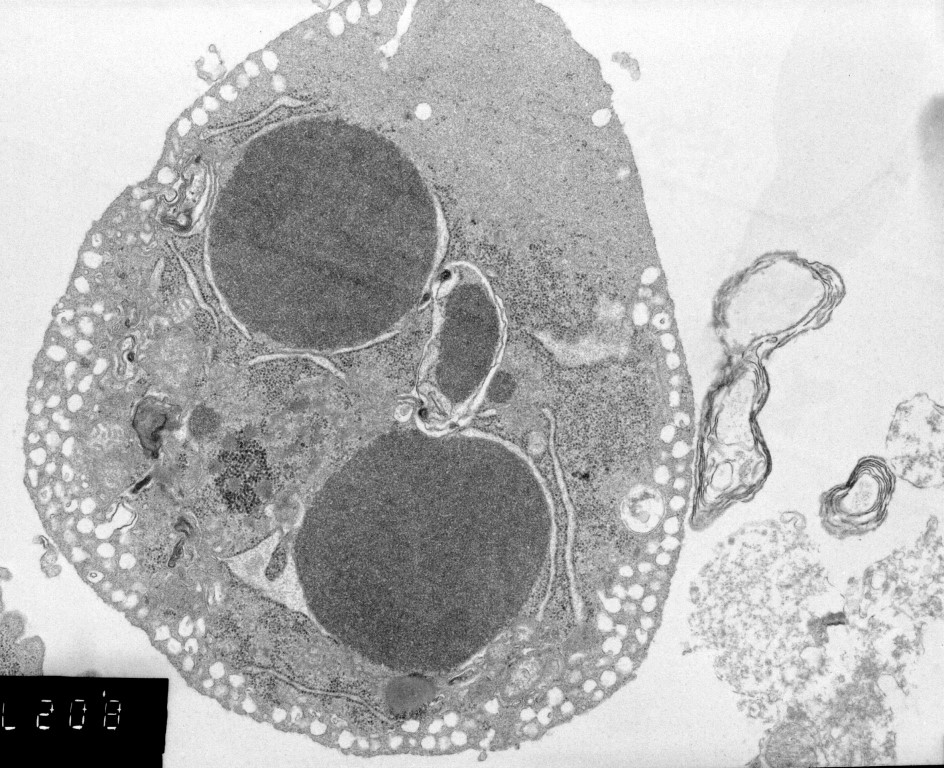

ملاحظة .. الصور صور حقيقية لعملية الاستماتة الذاتية او الموت المبرمج للخلايا